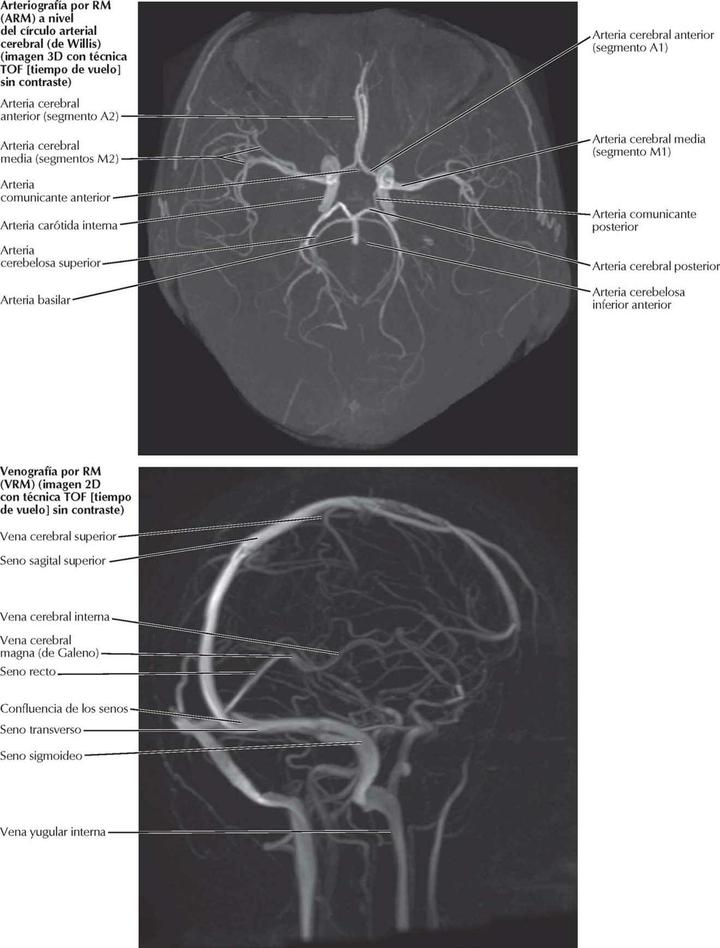

1. Angiografías por RM craneales (ARM y VRM)